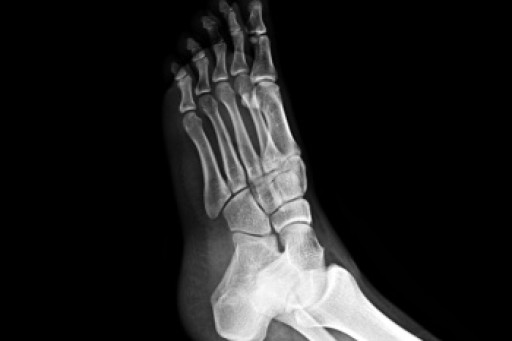

Causes and Risks of Foot Stress Fractures

Stress fractures in the feet are hairline cracks in the bone that often develop from repetitive force, rather than a single traumatic event. Stress fractures generally occur in the long bones of the foot, which endure significant impact during walking, running, and jumping. Overtraining, sudden increases in activity, or inadequate rest between workouts raise the risk. Foot structure also plays a role, with flat feet, high arches, or rigid arches contributing to uneven distribution of pressure that can stress certain bones. People with osteoporosis or low bone density are at higher risk, and nutritional deficiencies, such as inadequate calcium or vitamin D, may weaken bone strength. A podiatrist can confirm a diagnosis through examination and imaging, recommend appropriate footwear or orthotics, and advise whether surgery is required in severe cases. If you have symptoms of stress fractures in your feet, it is suggested that you make an appointment with a podiatrist for an exam, diagnosis, and treatment.